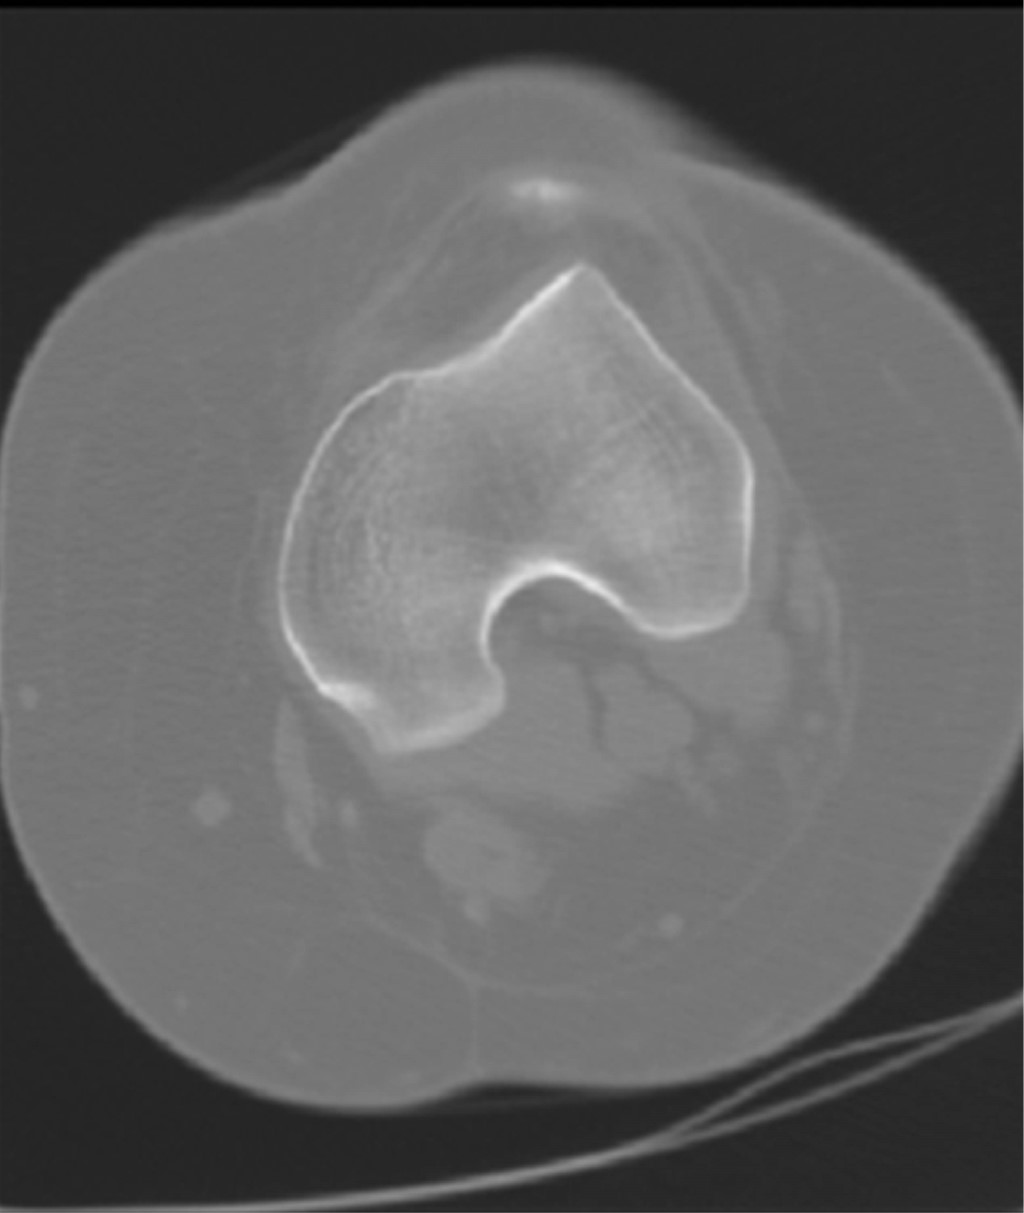

La alineación del mecanismo extensor se analiza con la tomografía computarizada midiendo la distancia de la tuberosidad tibial a la tróclea femoral (TT-TG), siendo esta misma más confiable que la medición del ángulo Q. El protocolo de tomografía computarizada superpone dos cortes, el primero a través del punto más proximal en la tróclea femoral (corte de referencia, donde la muesca del intercóndilo posterior se muestra como un arco romano) y el segundo corte a través del punto más proximal de la tuberosidad anterior de la tibia.13 Esta medida se obtiene mediante la superposición del corte axial que representa mejor la tróclea femoral y el corte axial más proximal que pasa a través de la tuberosidad tibial anterior (Figura 3). Se trazan dos líneas, una a partir de la parte inferior de la tróclea femoral y otra a través del centro de la tuberosidad tibial anterior, ambas perpendiculares a la línea condílea posterior. Esta distancia es medida en milímetros (mm). Cuando esta distancia es mayor de 20 mm predispone a la luxación rotuliana, por lo que se debería considerar realizar una osteotomía de la TAT y trasladarla a una posición más medial (en un sentido latero-medial), hasta llevar la distancia de TT-TG a un valor de 15 mm (el valor normal de esta distancia con la rodilla en extensión completa es entre 10 y 15 mm). La precisión de esta medida le permite al cirujano proponer una corrección precisa y evitar tanto una hipocorrección como una hipercorrección en la osteotomía.

Figura 1

Figura 2

Figura 3

Figura 4